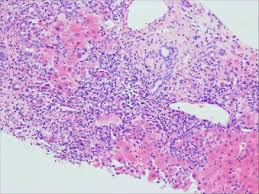

Autoimmune hepatitis is a chronic, inflammatory disease of the liver that is characterized by circulating autoantibodies and elevated serum globulin levels. The treatment of autoimmune hepatitis begins with seeking medical. Common initial symptoms include fatigue or muscle aches or signs of acute liver inflammation. How is autoimmune hepatitis treated? However, 50 years later aih still remains a major diagnostic and therapeutic challenge. How is autoimmune hepatitis diagnosed? Autoimmune hepatitis (aih) was the first liver disease for which an effective therapeutic intervention, corticosteroid treatment, was convincingly demonstrated in controlled clinical trials. Autoimmune hepatitis is a type of chronic liver inflammation that responds well to immunosuppressive medications, but may require liver transplant. There are 2 types of autoimmune hepatitis: Autoimmune hepatitis occurs worldwide but the exact incidence and prevalence of the disease in the united states is unknown. What websites do you recommend? How common is autoimmune hepatitis? Your healthcare provider will look at your health history the goal of treatment is to control the disease and to reduce or get rid of any symptoms (be in remission).

Autoimmune hepatitis is a chronic disease of unknown cause, characterized by continuing hepatocellular inflammation and necrosis and has a tendency to progress to cirrhosis. Conventional medical treatment involves the use of corticosteroids, either alone or in combination with the drug azathioprine have been the standard drug treatment for many years. A lot of the fundamental. Autoimmune hepatitis can lead to cirrhosis and liver failure. Common initial symptoms include fatigue or muscle aches or signs of acute liver inflammation. How their aih responds to treatment. Read on to know more. Medications are given to reduce immunity as the. In this case the cells attack the liver & as a result your liver becomes inflamed, enlarged and eventually if you have it long enough or severe enough liver cirrhosis. There are various treatments available for a if they develop any complications. Because autoimmune hepatitis is chronic, (lasting for many years), if left untreated, it has the. Formulary drug information for this topic. Treatment of autoimmune hepatitis is based on the following:

Autoimmune hepatitis (aih) is an uncommon liver disease which is characterized by inflammation of the liver and/or liver damage caused by an attack on the liver by a person's own immune system.